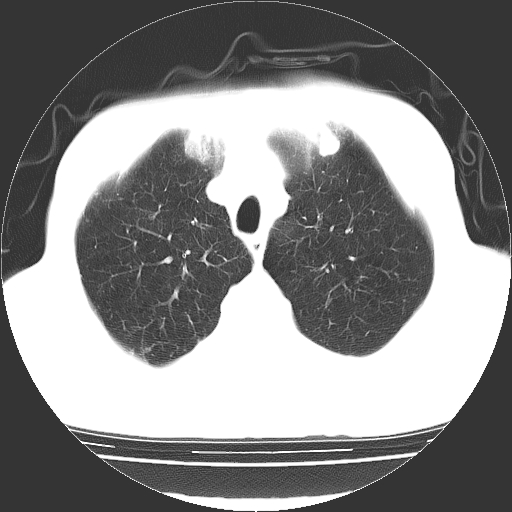

以下是引用hhcckk在2009-1-1 15:38:00的发言:[br]左下肺少许絮状模糊影--考虑感染[br]两肺散在小点状密度增高影--结合病史考虑矽肺?[br]气管壁钙化--可能由于老年退变性引起的